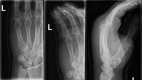

Isolated ulnopalmar dislocation of the fifth carpometacarpal joint

Dislocations of the carpometacarpal (CMC) joints are uncommon and are frequently missed on standard radiographs of the hand. Dislocations could be dorsal or palmar; dorsal dislocations are seen more frequently. Palmar dislocations can be either ulnopalmar or radiopalmar. Stable CMC dislocations could be successfully treated conservatively, while unstable dislocations are mostly treated operatively. The purpose of this report is to present a patient with an isolated ulnopalmar dislocation of the fifth CMC joint, satisfactorily treated with closed reduction and casting.